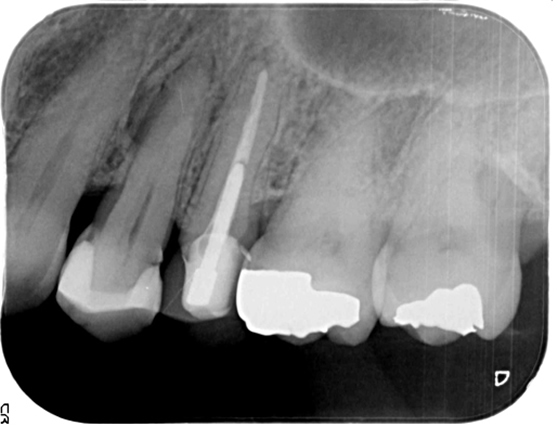

左上の5番が再治療しても歯茎の腫れが直らないとのことでしたが、当院での審査の結果、原因は左上4番(隣の歯)の神経が死んでしまっている事でした。左上4番の根幹治療を行い、その後症状は消失し経過は良好です。

![]() |